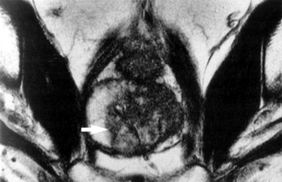

waste of time.  The NHS again swung into action. The MRI scan was done next month and turned

out to be fine. This time a splashed out and bought the CD of my images. The image to the right

is my pelvis showing the circular bladder and the prostate beneath it. The registrar went through it with

me and pronounced it OK.